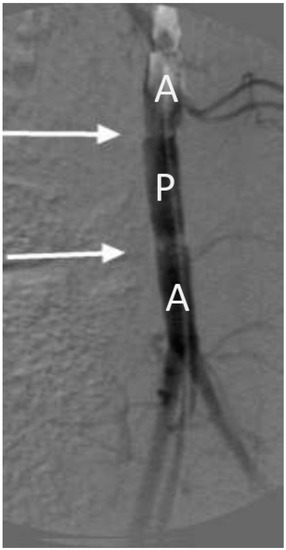

| Sample | Compliance, %/100 mmHg | |

|---|---|---|

| 3 Days | 30 Days | |

| Native aorta | 29 ± 1 | 24 ± 1 |

| BVP | 28 ± 1 | 22 ± 1 |